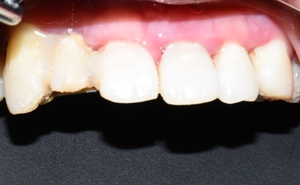

2-3달 만에 이정도로 공간이 없어지게 치아가 모아졌구요

화살표 되어있던 치아는 빼고 임시로 다른 치아를 붙여놓은 상태였습니다.

치아는 모아졌지만 아무래도 원래 본인 치아 모양이 있다보니 치아가 예쁜 모양은 아닙니다.

그후에 이 치아들을 깎아서

맞춤형으로 브릿지를 만들어서